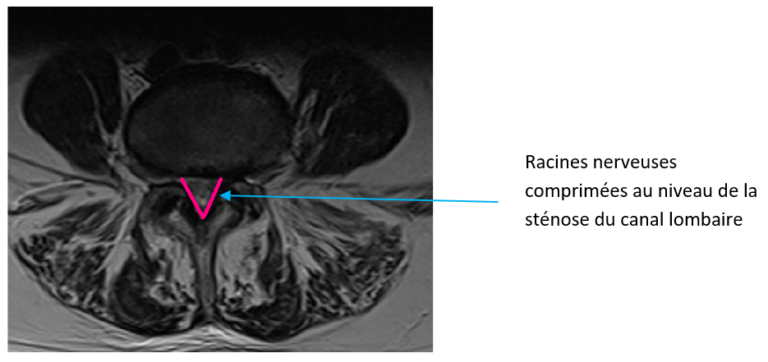

Canal Lombaire étroit - racines nerveuses comprimées